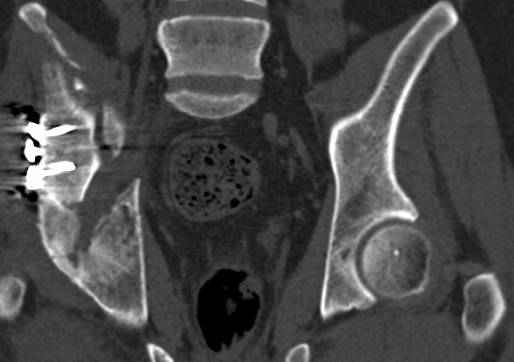

высылаю дополнительно сканы.

Судя по представленным реконструкциям (не очень хорошего качества - много наводок)

По отдельным срезам и тем более по реконструкции трудно судить о сращении крыла и задней колонны с осевым скелетом.

В большинстве случаев при двухколонных переломах

в итоге получается прочный бублик с дыркой. При эндопротезировании в дырку помещается головка, а чашка должна неплохо заклиниться в бублике.

Главное, чтобы бублик не был разорван, что не очень понятно на представленных снимках.

Поэтому хотелось бы дообследовать больного (разумеется включив стандартные проеции judet,и срезы показывающие сращение)

Хорошо бы на рентгенограммы взглянуть и побольше срезов по своду. С каким отломком головка контактирует и как ее состояние.

Из того минимума, что представлено, мне кажется, мы имеем дело с двухколонным переломом вертлужной впадины. Обычно медиальный (центральный) "вывих" головки встречаются в сложных двухколонных переломах со смещением.